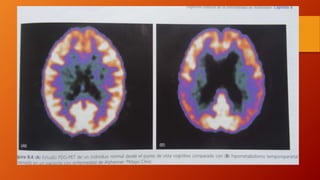

• Existen marcadores que permiten observar los depósitos de BA

cerebral in vivo , como el complejo B de Pittsburgh de uso

experimental. PET

• El SPECT muestra una reducción temprana del flujo sanguíneo

cerebral regional a nivel cingular posterior , después a nivel

temporal interno y después hay una hipoperfusión cortical

generalizada de predominio parieto-temporal.